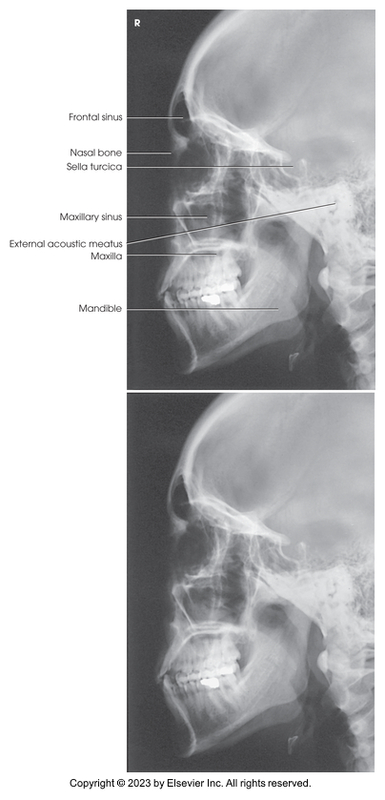

Lateral Projection of the Skull

Lateral Projection of Paranasal Sinuses

Lateral projection of skull

Lateral of the sinuses